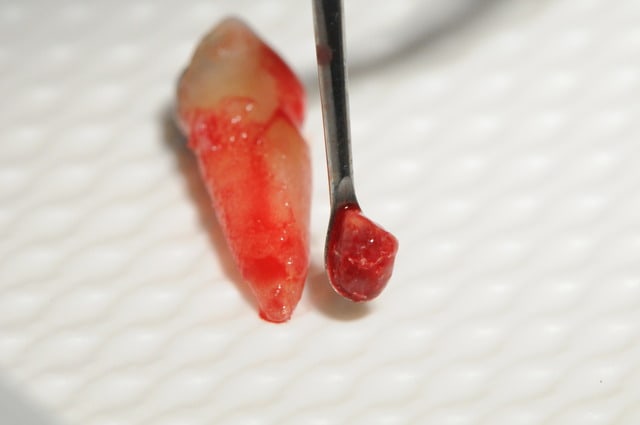

juste pour le fun.

résection apicale faites chez un endo exclusif au Luxembourg (attention les mauvaises langues, c'est pas l'Amibe!) il y a 3 trois ans.

je vous laisse juger...